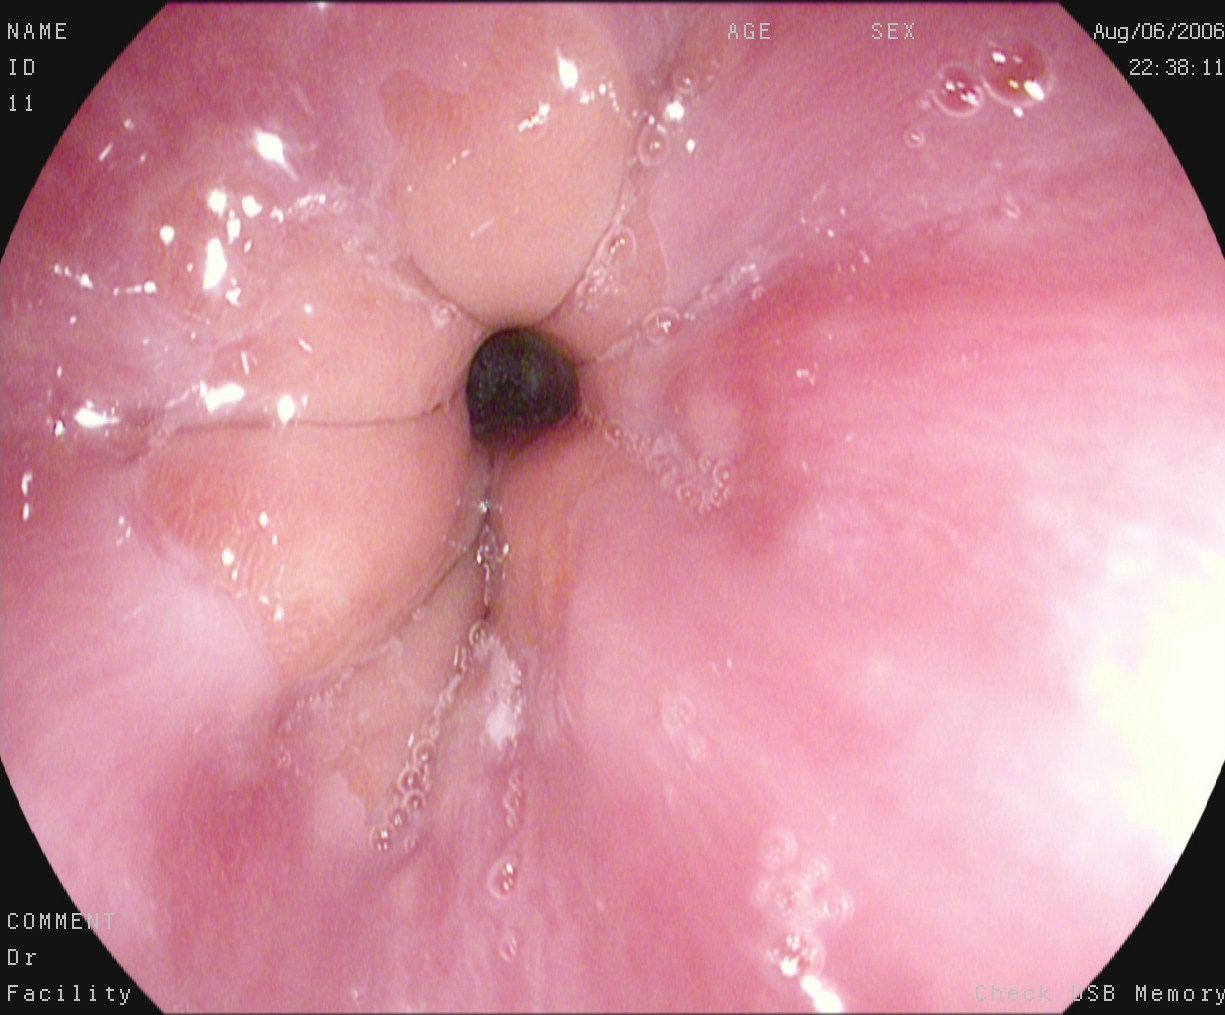

An automatic and efficient Computer-Aided Diagnosis (CAD) system in a clinic could assist medical experts during the endoscopic and colonoscopy procedure to improve the detection rate by finding unrecognized lesions and act as a second observer by providing better insights to the gastroenterologist concerning the presence and types of lesions. With this inspiration, we conducted five experiments to classify 161616 classes of GI tract conditions for the Medico Multimedia Task at MediaEval 2018 (Pogorelov et al., 2018b). One example for each of the 16 classes is depicted in Figure 1.

Figure 1. Sample images of GI findings. Each image represents one of the 16 classes from the dataset used for the Medico 2018 challenge (Pogorelov et al., 2017c, a).